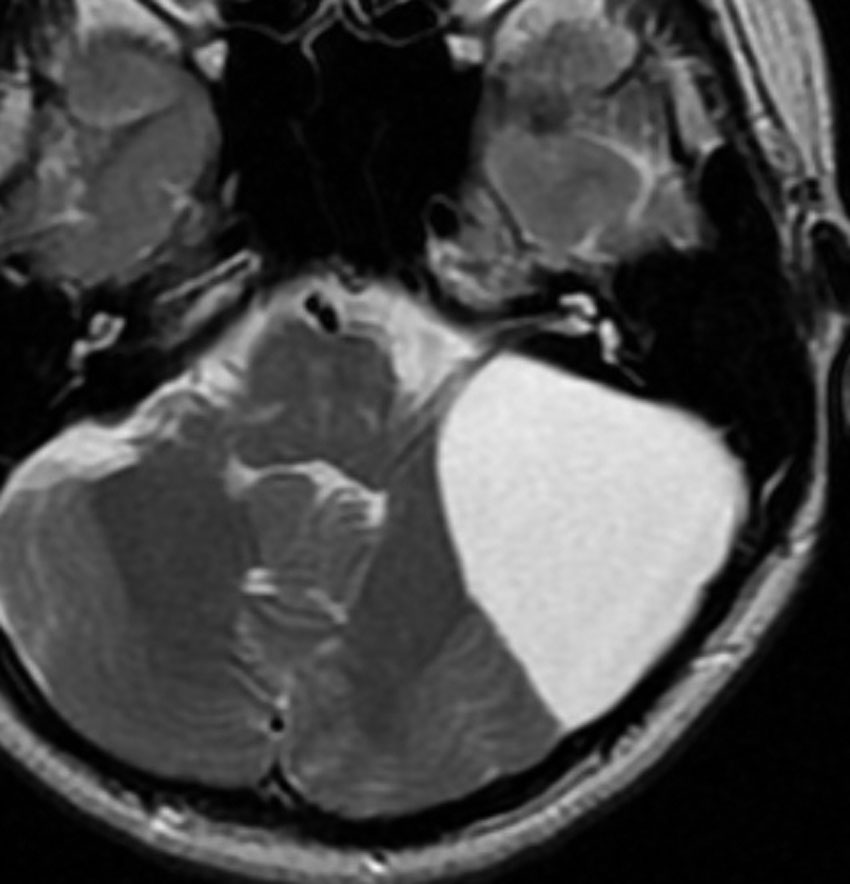

後頭下くも膜のう胞

脳神経圧迫(三叉神経,聴神経など)と小脳変形があるのですが,ほっておきます。